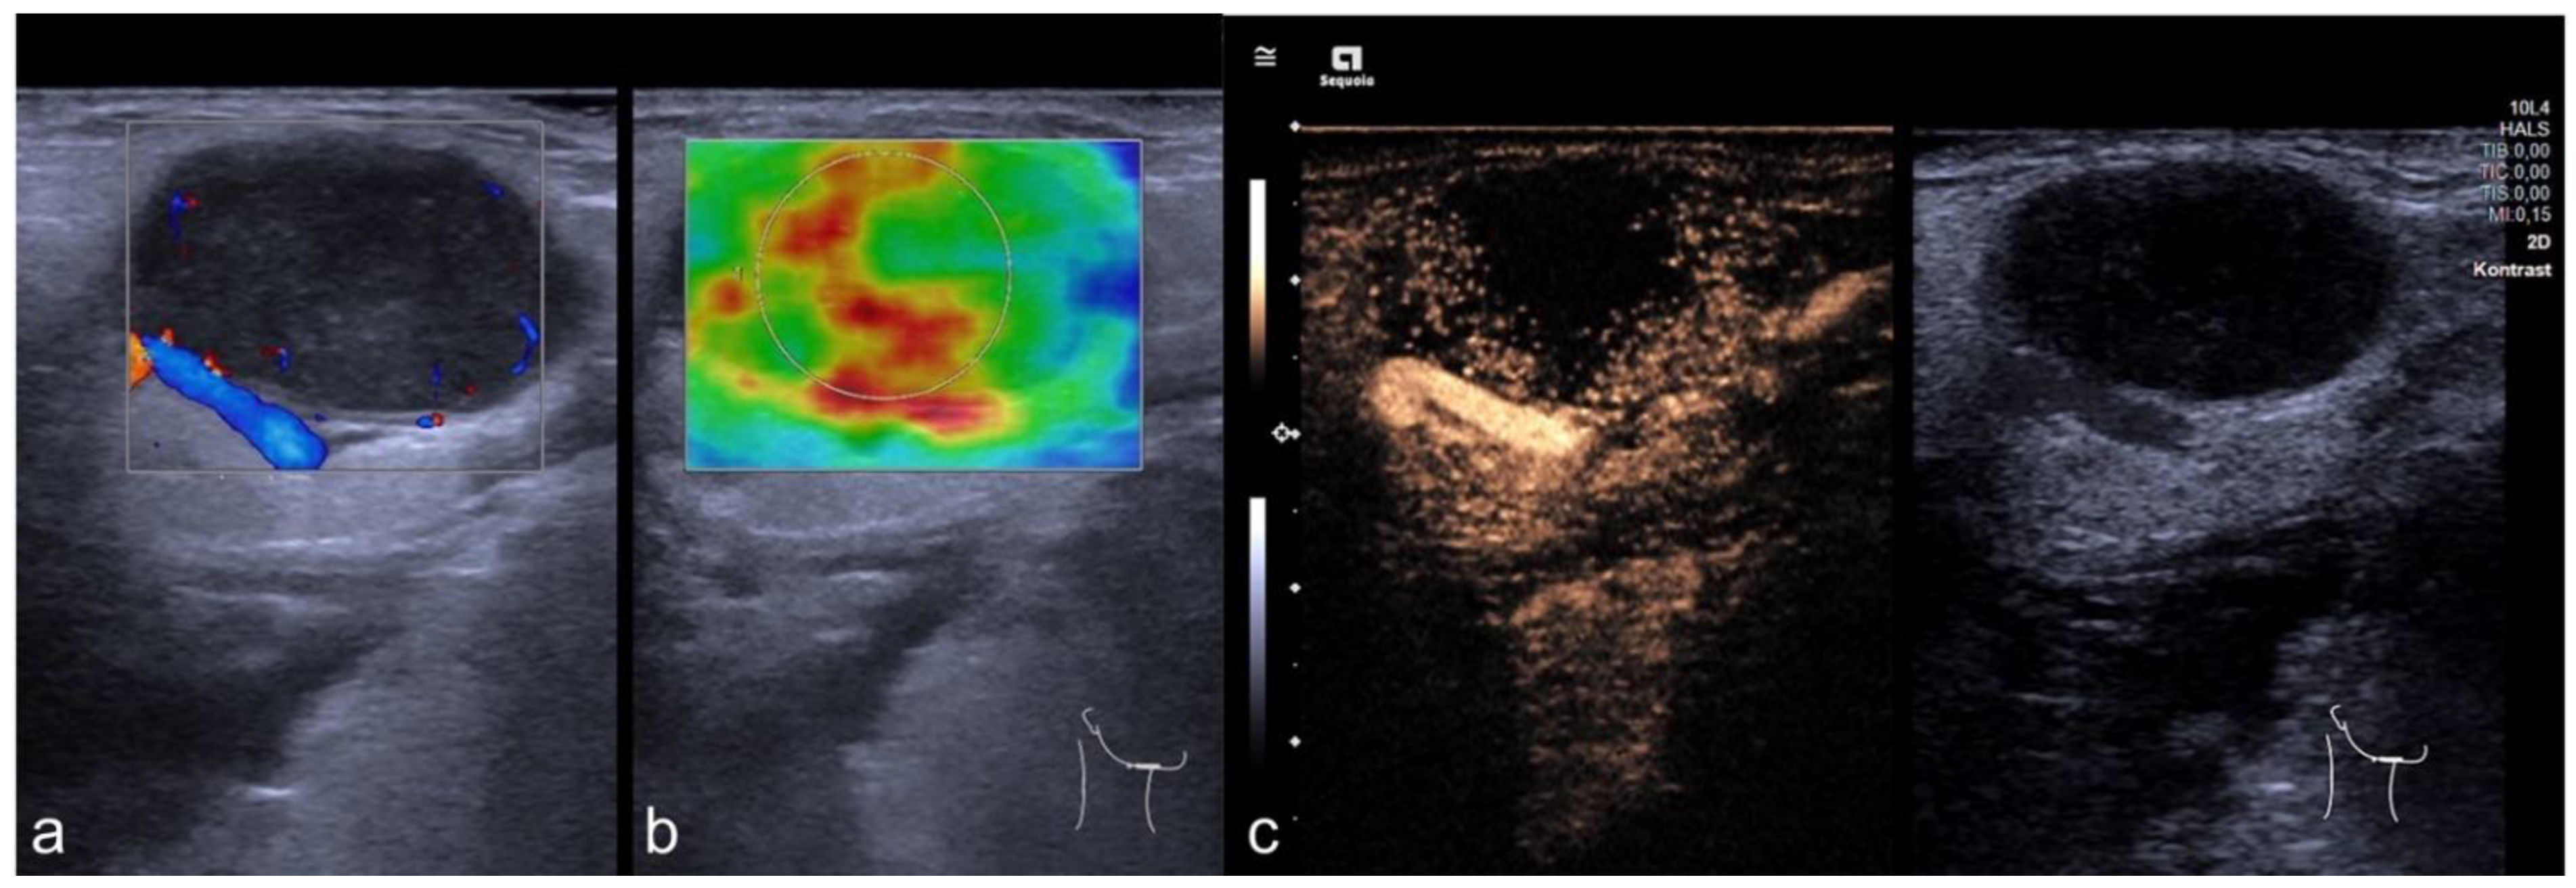

2.2. Imaging Protocol

2.3. Perfusion Analysis